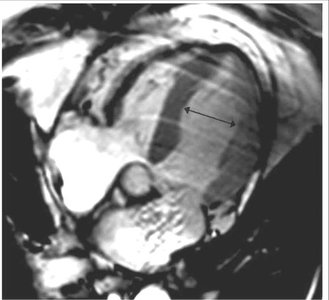

Takotsubo cardiomyopathy is an acute, reversible cardiac syndrome often triggered by emotional or physical stress. It is more prevalent in women and is characterized by transient left ventricular dysfunction, typically involving the apex (apical ballooning).

Imaging: Apical akinesis with preserved basal contraction

Pathophysiology | Ventricular dilation, reduced contractility | Transient apical ballooning, catecholamine surge |

Imaging | Dilated chambers, thin walls | Apical akinesis, ballooning |